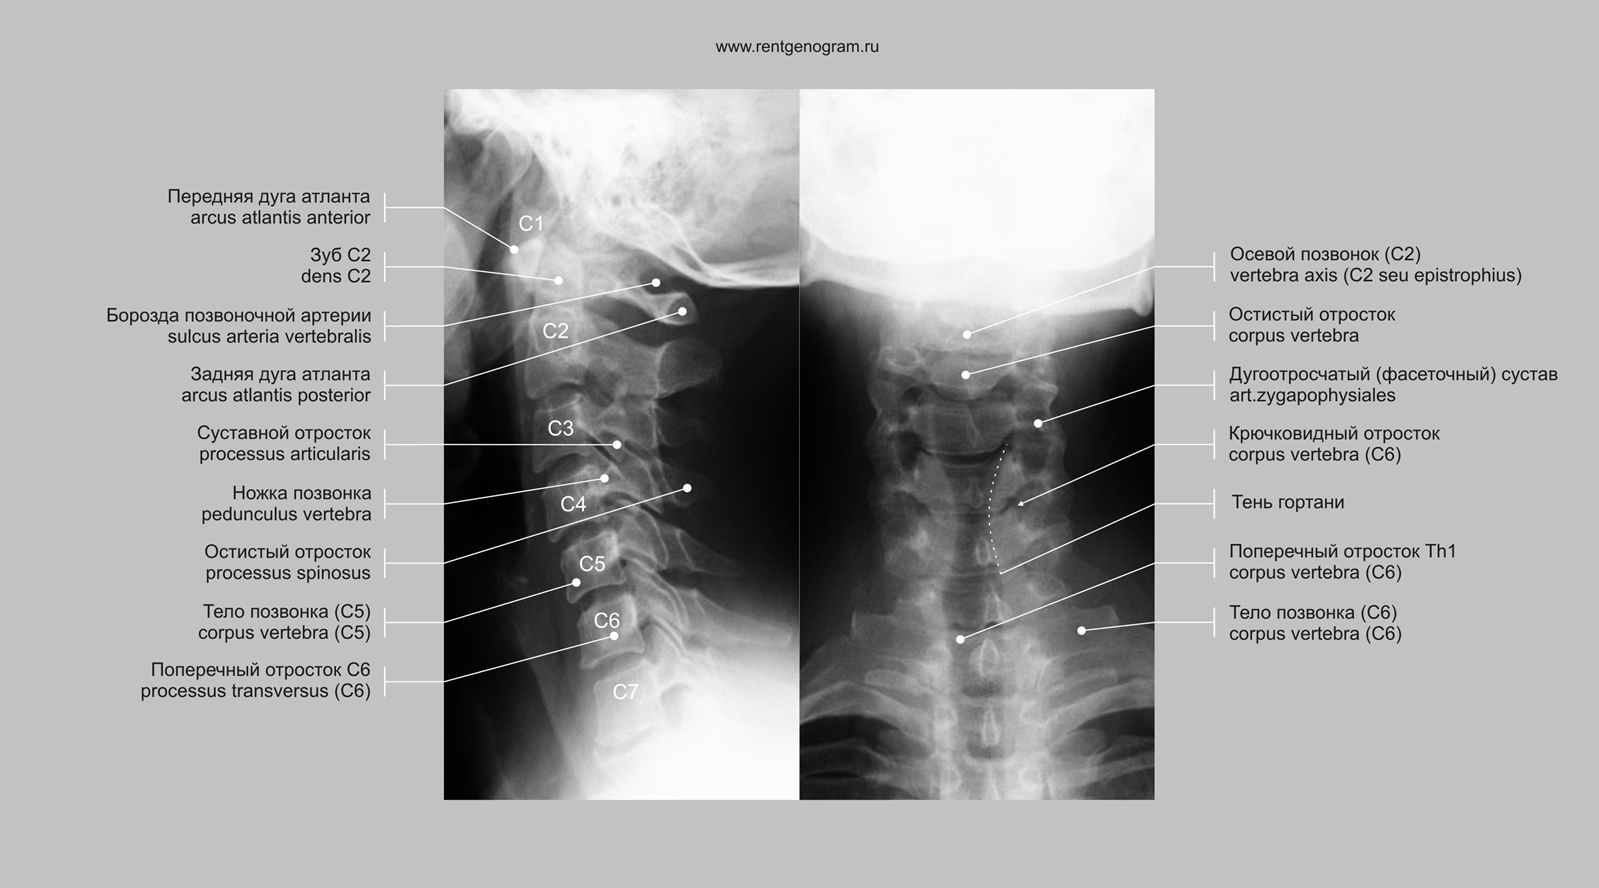

Рентген позвоночника в профиле

Проведение рентгенографии позвоночника в профиль является важным этапом в диагностике различных заболеваний позвоночника, таких как сколиоз, остеохондроз, травмы и др.

Исследование позволяет получить детальное изображение структуры позвоночного столба в боковой проекции, что обеспечивает возможность выявления патологий, незаметных на обычных снимках.

Рентген позвоночника в профиль помогает определить степень кривизны позвоночника, выявить деформации и изменения в структуре позвонков.